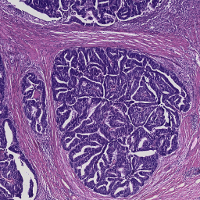

A set of 74 histological slides from 74 patients was prepared from surgically excised rectal carcinomas in patients who had not received neoadjuvant chemotherapy and/or radiotherapy. Slide preparation involved standard fixation of 2m tissue sections and H&E staining. Whole-slide scanning was performed at 200X magnification (pixel resolution = 0.455 m) using a Hamamatsu NanoZoomer 2.0-HT C9600-13 scanner (Herrsching, Germany), which produce 74 gigapixel whole-slide images. Manual annotations of 9 tissue classes were made by an expert using the open source software ASAP555github.com/GeertLitjens/ASAP developed in-house, which included: (i) tumor, (ii) stroma, (iii) necrosis, (iv) muscle, (v) healthy epithelium, (vi) fatty tissue, (vii) lymphocytes, (viii) mucus and (ix) blood cells (see Figure 2). All annotations were successively thoroughly checked by a pathologist and corrections were made when necessary. In the rest of the paper, we refer to this dataset as rectal cancer (RC) data.

Stain normalization (SN) involves transforming an image into another image , through the operation , where is a set of parameters extracted from a predefined template image and is the mapping function that matches the visual appearance of a given image to the template image. The parameters are generally defined to capture color information of the main stain components in the image (e.g. H and E). As a result, stain-normalized images will have a distribution of colors that resemble the ones of the template. In Figure 1, images from CRCt and their stain-normalized version based on the WSI template of Figure 2 are depicted.